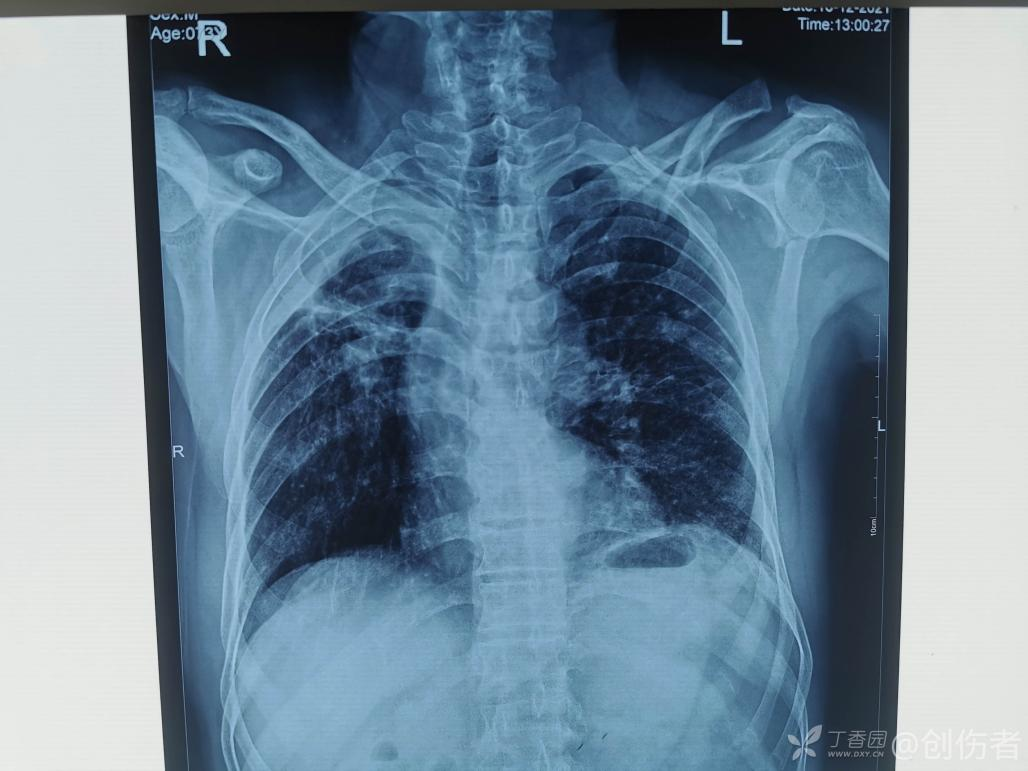

锁骨骨折大家一定都觉得很简单,但锁骨骨折也有一个并不少见的坑,看看下面的病例:

这个锁骨骨折简单吗?另一位网友分享:

等下,拍个双侧对比看看,锁骨骨折合并肩锁关节脱位,还好术前发现了 ……

第二、锁骨骨折一定要拍双侧对比片排除肩锁关节脱位。